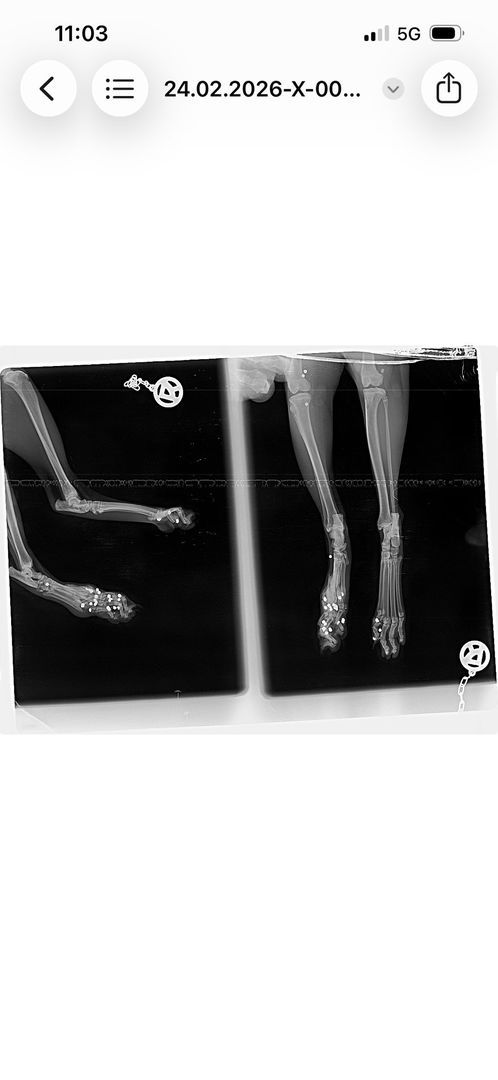

Nach diesem Zwischenfall waren alle vier Katzen verschwunden. Die Betreuerinnen suchten jeden Tag und stellten schließlich eine Kamera auf. Es wurde auch nochmals Kontakt mit dem Jäger aufgenommen – die Ungewissheit war unerträglich, man bat ihn um Ehrlichkeit, in der Hoffnung, Gewissheit zu bekommen und die Suche einstellen zu können. Doch der Jäger stritt weiterhin ab, auf die Katzen geschossen zu haben. Die Suche nach den Katzen ging also weiter, bis schließlich eines Tages eine der verschollenen Katzen auf den Kamera-Aufnahmen zu sehen war, zwei Wochen später tauchte eine zweite Katze auf den Aufnahmen auf. Nach insgesamt sechs Wochen Suche konnten zwei der Katzen endlich gesichert werden. Doch beim Tierarzt der nächste Schock: eine der Katzen war von mehreren Schrotkugeln getroffen worden und musste starke Schmerzen haben.

Nach Auswertung der Röntgenbilder liegt der Schluss nahe, dass die Katze von unten beschossen worden sein muss – die Betreuerinnen erzählen, dass die Katzen immer gerne auf den Balken im Stadl geschlafen haben. Es ist also ziemlich klar, was da passiert sein muss – und es stellt sich die Frage, wie abgebrüht man sein muss, um zu so etwas fähig zu sein. Bei einer Katze wurden die Kugeln, die unmittelbar unter der Haut lagen, mittlerweile entfernt – die tieferliegenden Kugeln sollen erst dann entfernt werden, wenn sie der Katze Probleme bereiten. Man will die Katze im Moment nicht noch mehr stressen. Der Kater, der ebenfalls gesichert werden konnte, ist bis heute so stark traumatisiert, dass eine Untersuchung bisher noch gar nicht durchgeführt werden konnte. Zumindest waren bei ihm aber keine Kugeln unter der Haut zu ertasten. Von den beiden anderen Katzen, die an der besagten Futterstelle versorgt worden waren, fehlt bis heute jede Spur. Es ist leider davon auszugehen, dass sie es nicht geschafft haben.

Hier noch weitere Röntgenbilder der angeschossenen Katze und das Schreiben der Staatsanwaltschaft Augsburg: